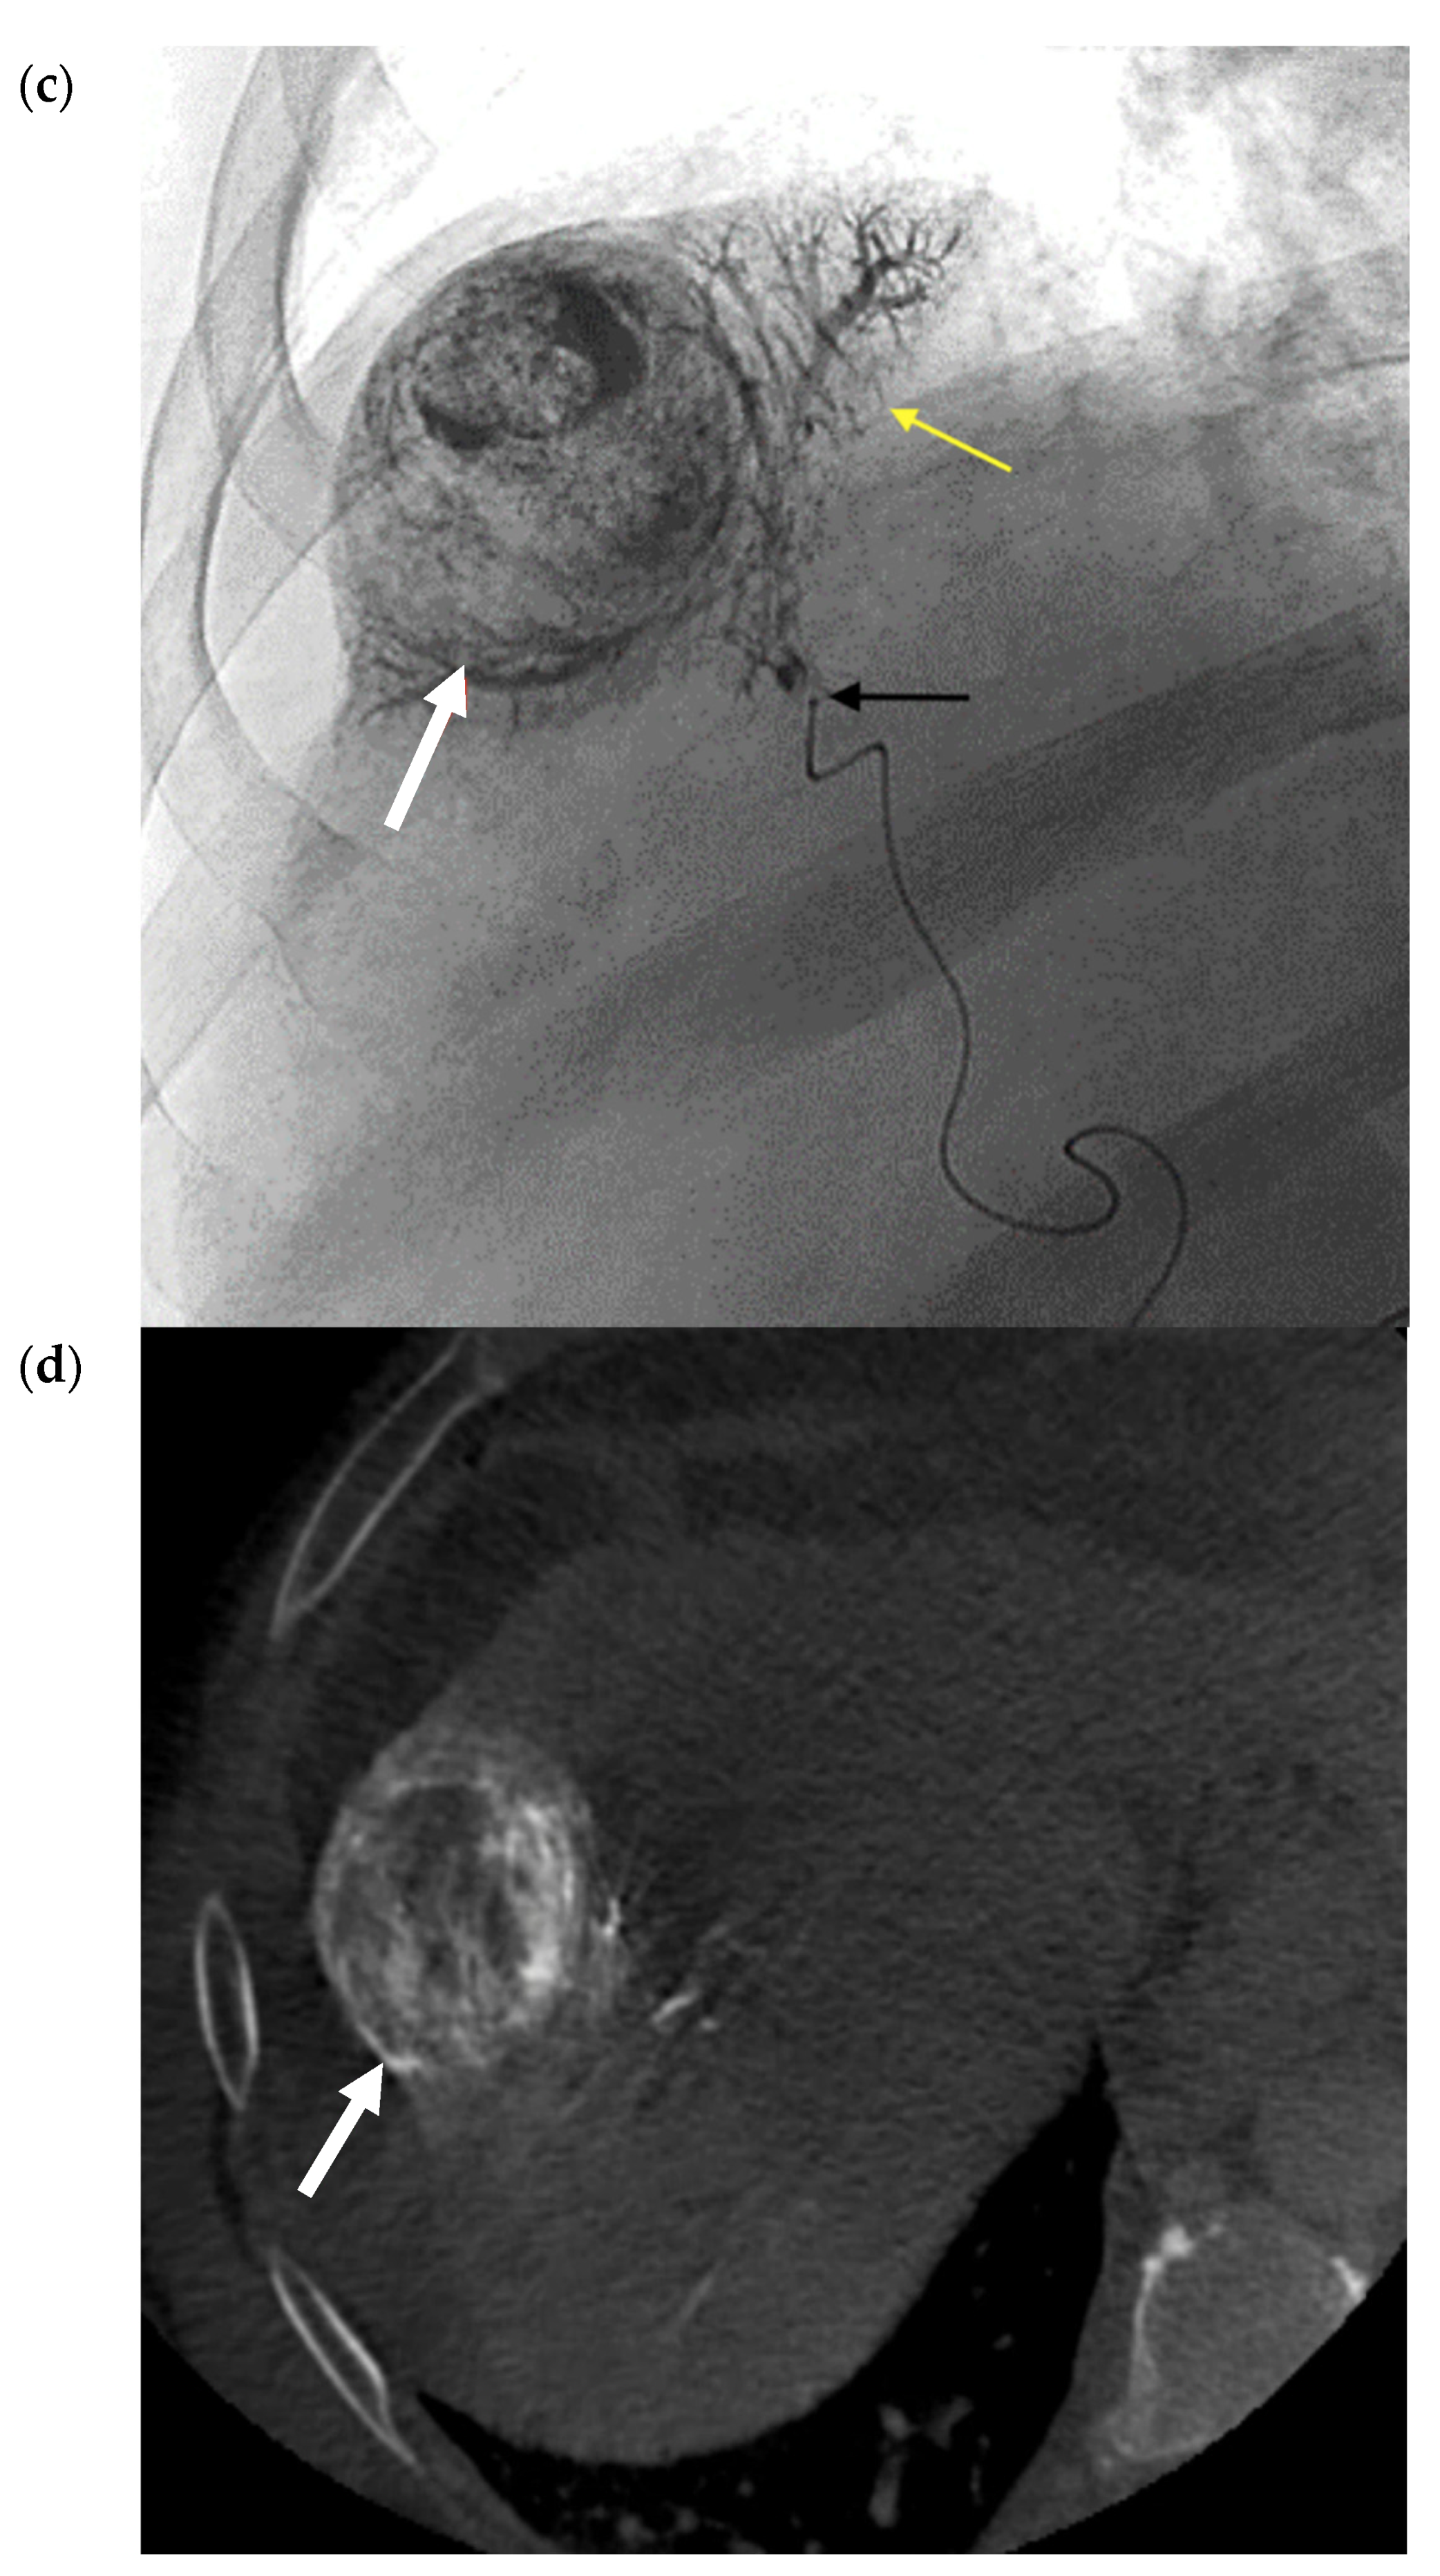

- Vouche, M.; Habib, A.; Ward, T.J.; Kim, E.; Kulik, L.; Ganger, D.; Mulcahy, M.; Baker, T.; Abecassis, M.; Sato, K.T.; et al. Unresectable solitary hepatocellular carcinoma not amenable to radiofrequency ablation: Multicenter radiology-pathology correlation and survival of radiation segmentectomy. Hepatology 2014, 60, 192–201. [Google Scholar] [CrossRef]

- Biederman, D.M.; Titano, J.J.; Korff, R.; Fischman, A.; Patel, R.S.; Nowakowski, F.S.; Lookstein, R.; Kim, E. Radiation Segmentectomy versus Selective Chemoembolization in the Treatment of Early-Stage Hepatocellular Carcinoma. J. Vasc. Interv. Radiol. 2018, 29, 30–37. [Google Scholar] [CrossRef]

- Lewandowski, R.; Gabr, A.; Abouchaleh, N.; Ali, R.; Al Asadi, A.; Mora, R.; Kulik, L.; Ganger, D.; Desai, K.; Thornburg, B.; et al. Radiation Segmentectomy: Potential Curative Therapy for Early Hepatocellular Carcinoma. Radiology 2018, 287, 1050–1058. [Google Scholar] [CrossRef]

- Padia, S.A.; Kwan, S.W.; Roudsari, B.; Monsky, W.L.; Coveler, A.; Harris, W.P. Superselective Yttrium-90 Radioembolization for Hepatocellular Carcinoma Yields High Response Rates with Minimal Toxicity. J. Vasc. Interv. Radiol. 2014, 25, 1067–1073. [Google Scholar] [CrossRef] [PubMed]